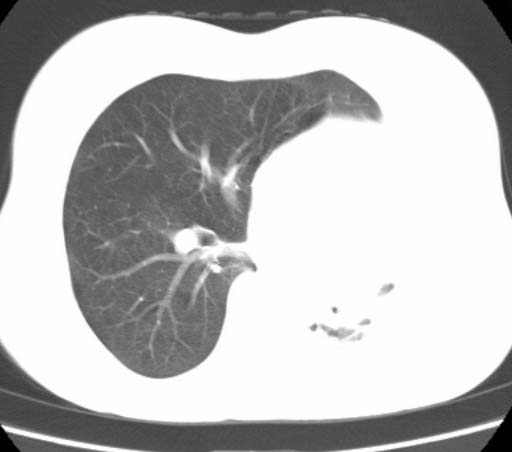

标题: CT25648:求教:是肺发育不全还是结核?

女  20岁。一月前咳血,诊“肺结核”抗痨治疗一月后,咳血停止,现复查。病人精神好。前后ct片对比未见明显变化。既往体检“正常”

1)考虑左肺结核并肺不张、支气管扩张。2)纵隔疝。

以前体检正常只能考虑左肺结核并肺不张、支气管扩张。2)纵隔疝。

考虑左肺结核,左肺毁损,纵膈左偏,既往体检正常不可靠,tb一个月也不会这个样子的,有钙化,应该病程较长,冰冻三尺非一日之寒!

考虑左肺结核,左肺毁损,纵膈左偏,既往体检正常不可靠,tb一个月也不会这个样子的,有钙化,应该病程较长,冰冻三尺非一日之寒